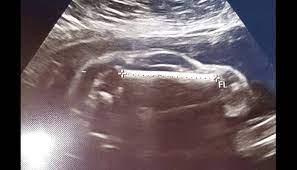

ਗਰਭਵਤੀ ਪਤਨੀ ਦੇ ਗਰਬ ਵਿਚ ਬੱਚੇ ਦੀ ਜਗ੍ਹਾ ਦਿਸੀ ਸਪੋਰਟਸ ਕਾਰ।

ਆਮ ਤੌਰ ’ਤੇ ਜਦੋਂ ਵੀ ਕੋਈ ਜੋੜਾ ਕਲੀਨਿਕ ’ਚ ਅਲਟਰਾਸਾਊਂਡ ਕਰਵਾਉਣ ਲਈ ਡਾਕਟਰ ਕੋਲ ਜਾਂਦਾ ਹੈ, ਤਾਂ ਉਨ੍ਹਾਂ ਦੇ ਮਨ ਵਿਚ ਕੁਝ ਸਵਾਲ ਹੁੰਦੇ ਹਨ। ਉਨ੍ਹਾਂ ਦਾ ਹੋਣ ਵਾਲਾ ਬੱਚਾ ਪੇਟ ’ਚ ਕੀ ਕਰ ਰਿਹਾ ਹੋਵੇਗਾ, ਕਿਹੋ ਜਿਹਾ ਦਿਸਦਾ ਹੋਵੇਗਾ?ਪਰ ਅਜਿਹਾ ਲੱਗ ਰਿਹਾ ਹੈ ਕਿ ਅੱਜ-ਕੱਲ ਦੁਨੀਆ ’ਚ ਕੁਝ ਜ਼ਿਆਦਾ ਹੀ ਅਜੀਬ ਘਟਨਾਵਾਂ ਹੁੰਦੀਆਂ ਜਾ ਰਹੀਆਂ ਹਨ। ਤੁਸੀਂ ਸੋਚੋ ਕਿ ਤੁਸੀਂ ਆਪਣੀ ਪਤਨੀ ਨੂੰ ਲੈ ਕੇ ਡਾਕਟਰ ਕੋਲ ਜਾਂਦੇ ਹੋ ਅਤੇ ਉਹ ਕਹੇ ਕਿ ਮੁਬਾਰਕ ਹੋਵੇ, ਤੁਸੀਂ ਸਪੋਰਟਸ ਕਾਰ ਦੇ ਪਿਤਾ ਬਣਨ ਵਾਲੇ ਹੋ।ਉਸ ਸਮੇਂ ਤੁਹਾਡੀ ਹਾਲਤ ਸੱਚਮੁੱਚ ਦੇਖਣ ਵਾਲੀ ਹੋਵੇਗੀ। ਅਜਿਹਾ ਹੀ ਕੁਝ ਇਕ ਵਿਅਕਤੀ ਨਾਲ ਹੋਇਆ, ਜਦੋਂ ਉਹ ਆਪਣੀ ਪਤਨੀ ਨੂੰ ਡਾਕਟਰ ਕੋਲ ਲੈ ਕੇ ਗਿਆ। ਫੇਸਬੁੱਕ ’ਤੇ ਇਕ ਯੂਜ਼ਰ ਨੇ ਇਕ ਪੋਸਟ ਪਾ ਕੇ ਇਹ ਜਾਣਕਾਰੀ ਦਿੱਤੀ। ਜਦੋਂ ਉਹ ਆਪਣੀ ਗਰਭਵਤੀ ਪਤਨੀ ਦਾ ਚੈਕਅੱਪ ਕਰਵਾਉਣ ਲਈ ਡਾਕਟਰ ਕੋਲ ਗਿਆ ਤਾਂ ਅਲਟਰਾਸਾਊਂਡ ’ਚ ਪੇਟ ਦੇ ਅੰਦਰ ਸਪੋਰਟਸ ਕਾਰ ਵਰਗੀ ਸ਼ਕਲ ਦਿਖਾਈ ਦਿੱਤੀ। ਇਹ ਦੇਖ ਕੇ ਪਤੀ-ਪਤਨੀ ਦੋਵੇਂ ਹੈਰਾਨ ਰਹਿ ਗਏ।ਜਦੋਂ ਪਤਾ ਲੱਗਾ ਕਿ ਪੇਟ ’ਚ ਕੋਈ ਕਾਰ ਨਹੀਂ ਹੈ, ਇਹ ਉਸ ਦਾ ਬੱਚਾ ਹੈ, ਬੱਸ ਉਸ ਦੀ ਸ਼ਕਲ ਇਸ ਸਮੇਂ ਕਾਰ ਵਰਗੀ ਲੱਗ ਰਹੀ ਹੈ, ਤਾਂ ਉਨ੍ਹਾਂ ਦੀ ਜਾਨ ਵਿਚ ਜਾਨ ਆਈ। ਉਨ੍ਹਾਂ ਦਾ ਕਹਿਣਾ ਸੀ ਕਿ ਇਕ ਤਾਂ ਉਹ ਪਹਿਲਾਂ ਹੀ ਹੈਰਾਨ ਸਨ ਕਿ ਉਨ੍ਹਾਂ ਦੀ ਪਤਨੀ ਇੰਨੀ ਜਲਦੀ ਗਰਭਵਤੀ ਕਿਵੇਂ ਹੋ ਗਈ, ਜਦੋਂ ਉਨ੍ਹਾਂ ਦੇ ਪਹਿਲੇ ਬੱਚੇ ਦੇ ਜਨਮ ਨੂੰ 6 ਮਹੀਨੇ ਹੀ ਹੋਏ ਹਨ ਅਤੇ ਹੁਣ ਪੇਟ ’ਚ ਸਪੋਰਟਸ ਕਾਰ ਦਿਖਾਈ ਦੇ ਰਹੀ ਹੈ। ਉਨ੍ਹਾਂ ਨੇ ਤੁਰੰਤ ਅਲਟਰਾਸਾਊਂਡ ਦੀਆਂ ਤਸਵੀਰਾਂ ਸੋਸ਼ਲ ਮੀਡੀਆ ’ਤੇ ਸ਼ੇਅਰ ਕੀਤੀਆਂ ਜਿਸ ਤੇ ਕਈ ਲੋਕ ਨੇ ਤੰਜ ਵੀ ਕਸੇ।